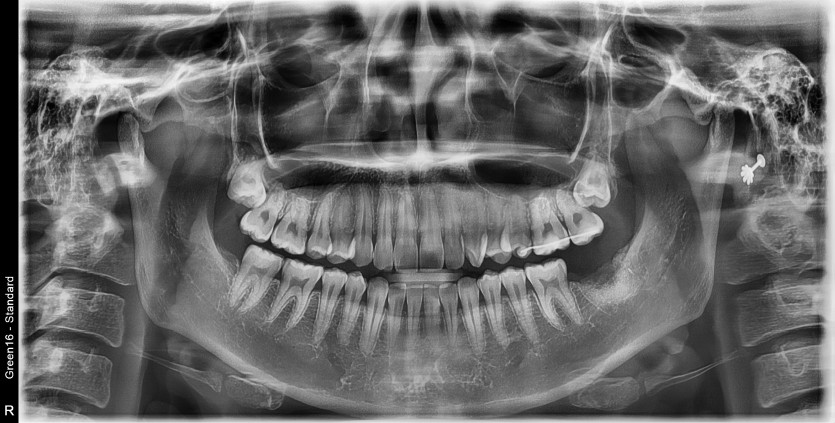

#38 사랑니 발치

구강 외과 전문의가 당일 발치 했습니다.